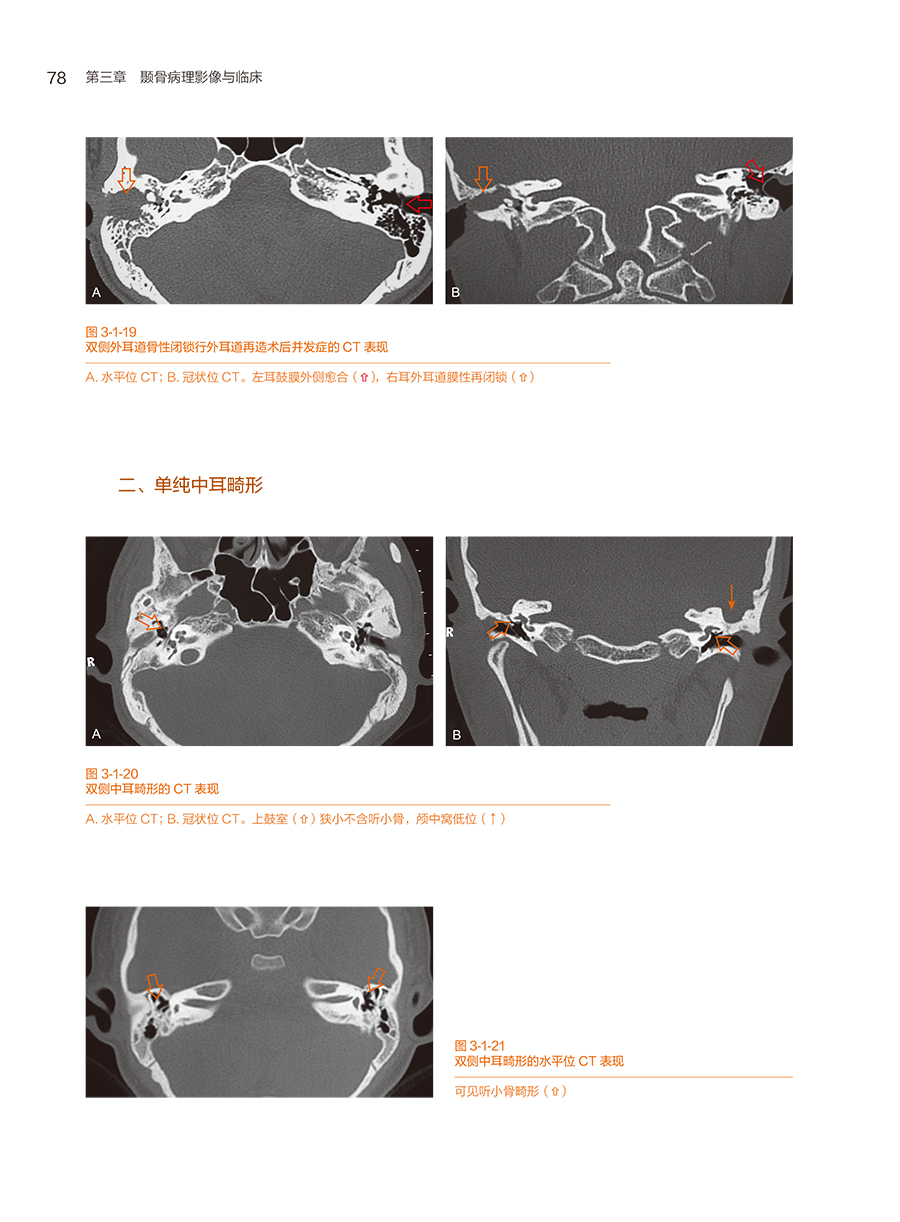

第一节 先天性颞骨畸形及解剖变异

一、先天性外耳道闭锁(或狭窄)伴中耳畸形及术后并发症

二、单纯中耳畸形